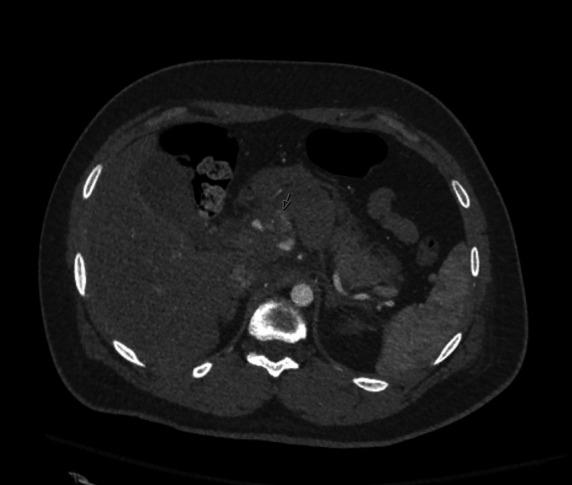

Management of a common hepatic artery pseudoaneurysm after blunt trauma.

Trauma Surg Acute Care Open. 2022 Apr 19;7(1):e000909. doi: 10.1136/tsaco-2022-000909. eCollection 2022.

https://cdn.ncbi.nlm.nih.gov/pmc/blobs/8ec9/9020312/edf8298a0791/tsaco-2022-000909f02.jpg

https://cdn.ncbi.nlm.nih.gov/pmc/blobs/8ec9/9020312/5a3a46649bbb/tsaco-2022-000909f01.jpg